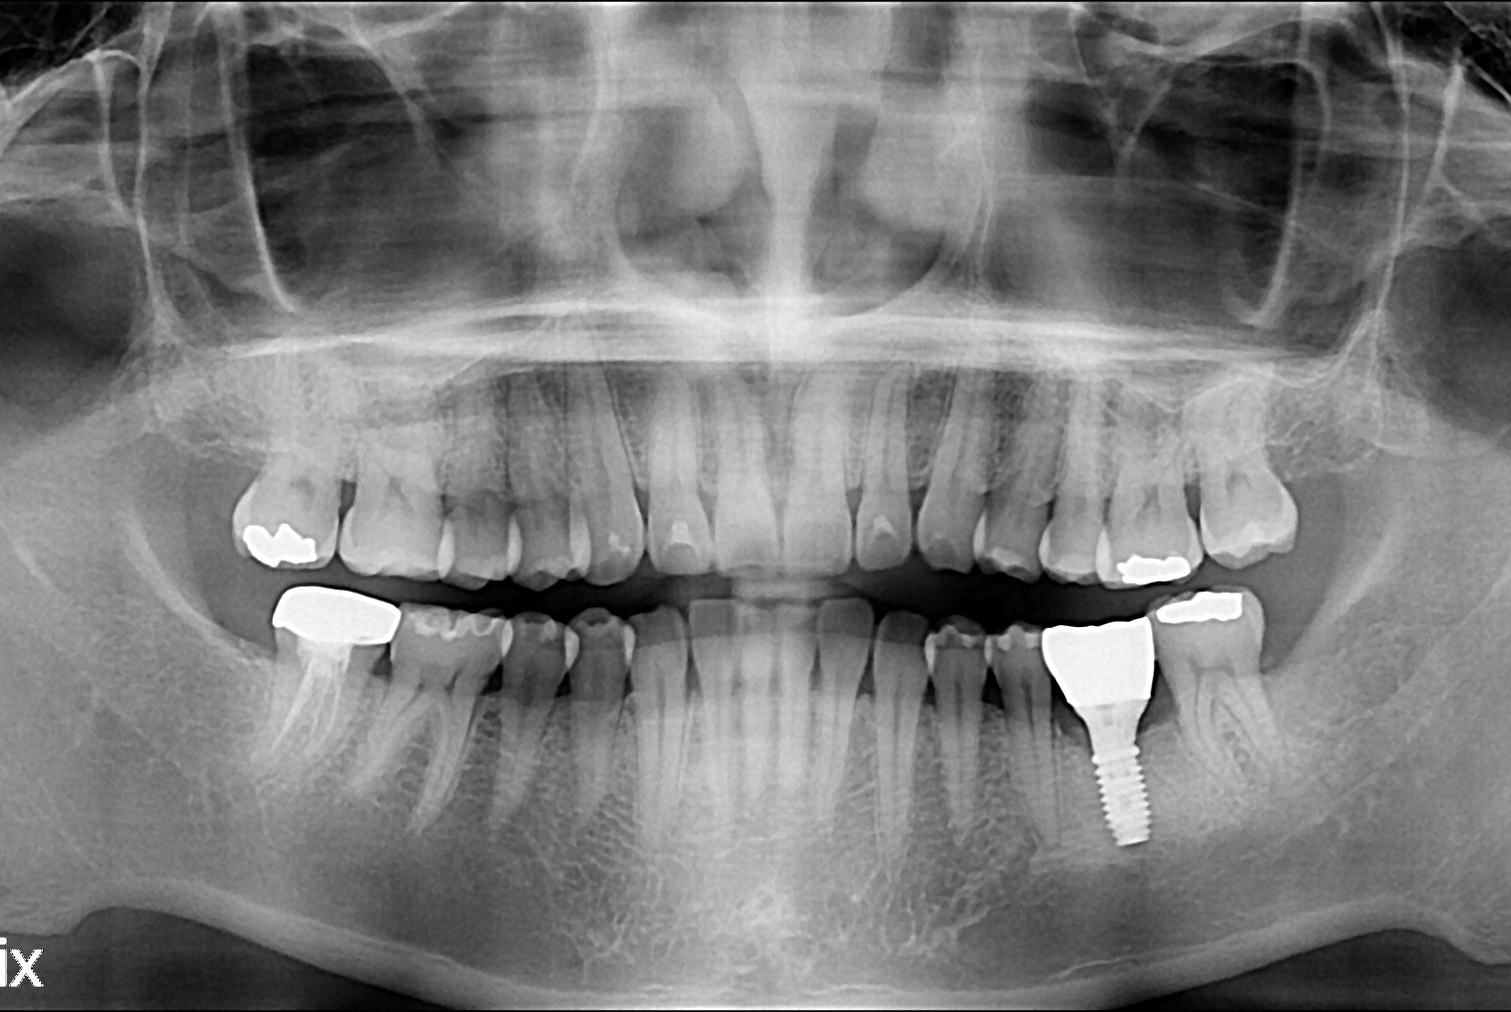

치료전 : 2016-01-21

치료후 : 2016-02-26

세종치과는 많은 환자와 다양한 케이스를 바탕으로 항상 편안한 임플란트 수술을 제공하고자 노력하고,

오래동안 튼튼히 쓸 수 있는 임플란트 수술을 가장 큰 목표로 삼고 있습니다